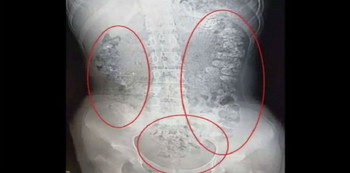

Menurut media lokal China, The Paper, rasa sakit yang diderita sang gadis akhirnya membuat dokter melakukan CT Scan atau pemindaian tubuh untuk mengetahui apa yang dialami.

Lewat pemeriksaan tersebut akhirnya memperlihatkan ada ratusan benda kecil yang memenuhi sebagian besar organnya, mulai dari perut hingga usus besar dan anusnya. Benda kecil yang memenuhi tubuh sang gadis ternyata tak lain adalah butiran bubble tea.

Kemudian, dr. Meta menanbahkan, “Memang jika dilihat dari hasil foto rontgennya itu gambaran konstipasi. Gambaran X ray-nya memang seperti itu. Tapi kalau dibilang pearl-nya nyangkut di usus yang kelihatan di X ray sepertinya, sih, bukan.”